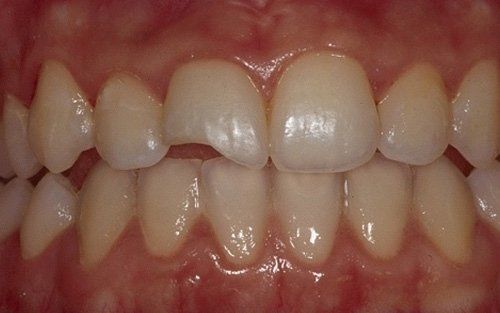

Frequenti, in età pediatrica, sono i traumi (sportivi e non). Come conseguenza i denti anteriori superiori (ovvero gli incisivi) sono i più esposti all’evento che può esitare in una frattura della corona con o senza il coinvolgimento della polpa, nella necrosi del dente (che può avvenire, più facilmente, senza alcuna frattura della corona dentale), oppure in quel panel di complicanze che vanno dalla lussazione ai traumi intrusivi o estrusivi, fino all’ avulsione, cioè la fuoriuscita completa del dente dall’alveolo.